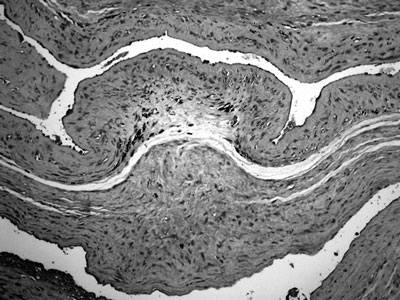

Εικόνα 1. Χοριοαμνιονίτιδα. Oξεία φλεγμονώδης διήθηση σε όλο το πάχος του χοριονικού πετάλου με ουδετερόφιλα πολυμορφοπύρηνα (Χρώση αιματοξυλίνης- ηωσίνης. Αρχική μεγέθυνση 40).

Η χοριοαμνιονίτιδα, δηλ. η οξεία φλεγμονή των υμένων, συνδυάζεται με την ανιούσα λοίμωξη και την πρόκληση ενδομήτριας πνευμονίας. Η θολότητα των μεμβρανών οφείλεται στη διήθησή τους από πολυμορφοπύρηνα (εικόνα 1) και στην ύπαρξη πυωδών εξιδρωμάτων. Η ρήξη των υμένων και η πρόωρη πρόκληση τοκετού αποτελούν συχνές επιπλοκές της χοριοαμνιονίτιδας και συμβαίνουν μέσω της απελευθέρωσης κυτοκινών, ιντερλευκινών και της σύνθεσης κολλαγενάσης ή μέσω της αυξημένης σύνθεσης προσταγλανδίνης. Όταν η διάγνωση τίθεται μόνο ιστολογικά χωρίς προηγούμενη εκδήλωση συμπτωμάτων, πρόκειται για «σιωπηλή» φλεγμονή. H χοριοαμνιονίτιδα, όχι μόνο παρατηρείται σε πολύ μεγάλο ποσοστό (55%) στις περιπτώσεις πρόωρων τοκετών,(10) αλλά αποτελεί και τον σημαντικότερο αιτιολογικό παράγοντα πρόκλησής τους πριν τη συμπλήρωση των 30 εβδομάδων. Συνδυάζεται συχνά με τη φθαρτίτιδα, με το οπισθοπλακούντιο αιμάτωμα και με την πρόωρη αποκόλληση, και υπάρχει η πιθανότητα υποτροπής.